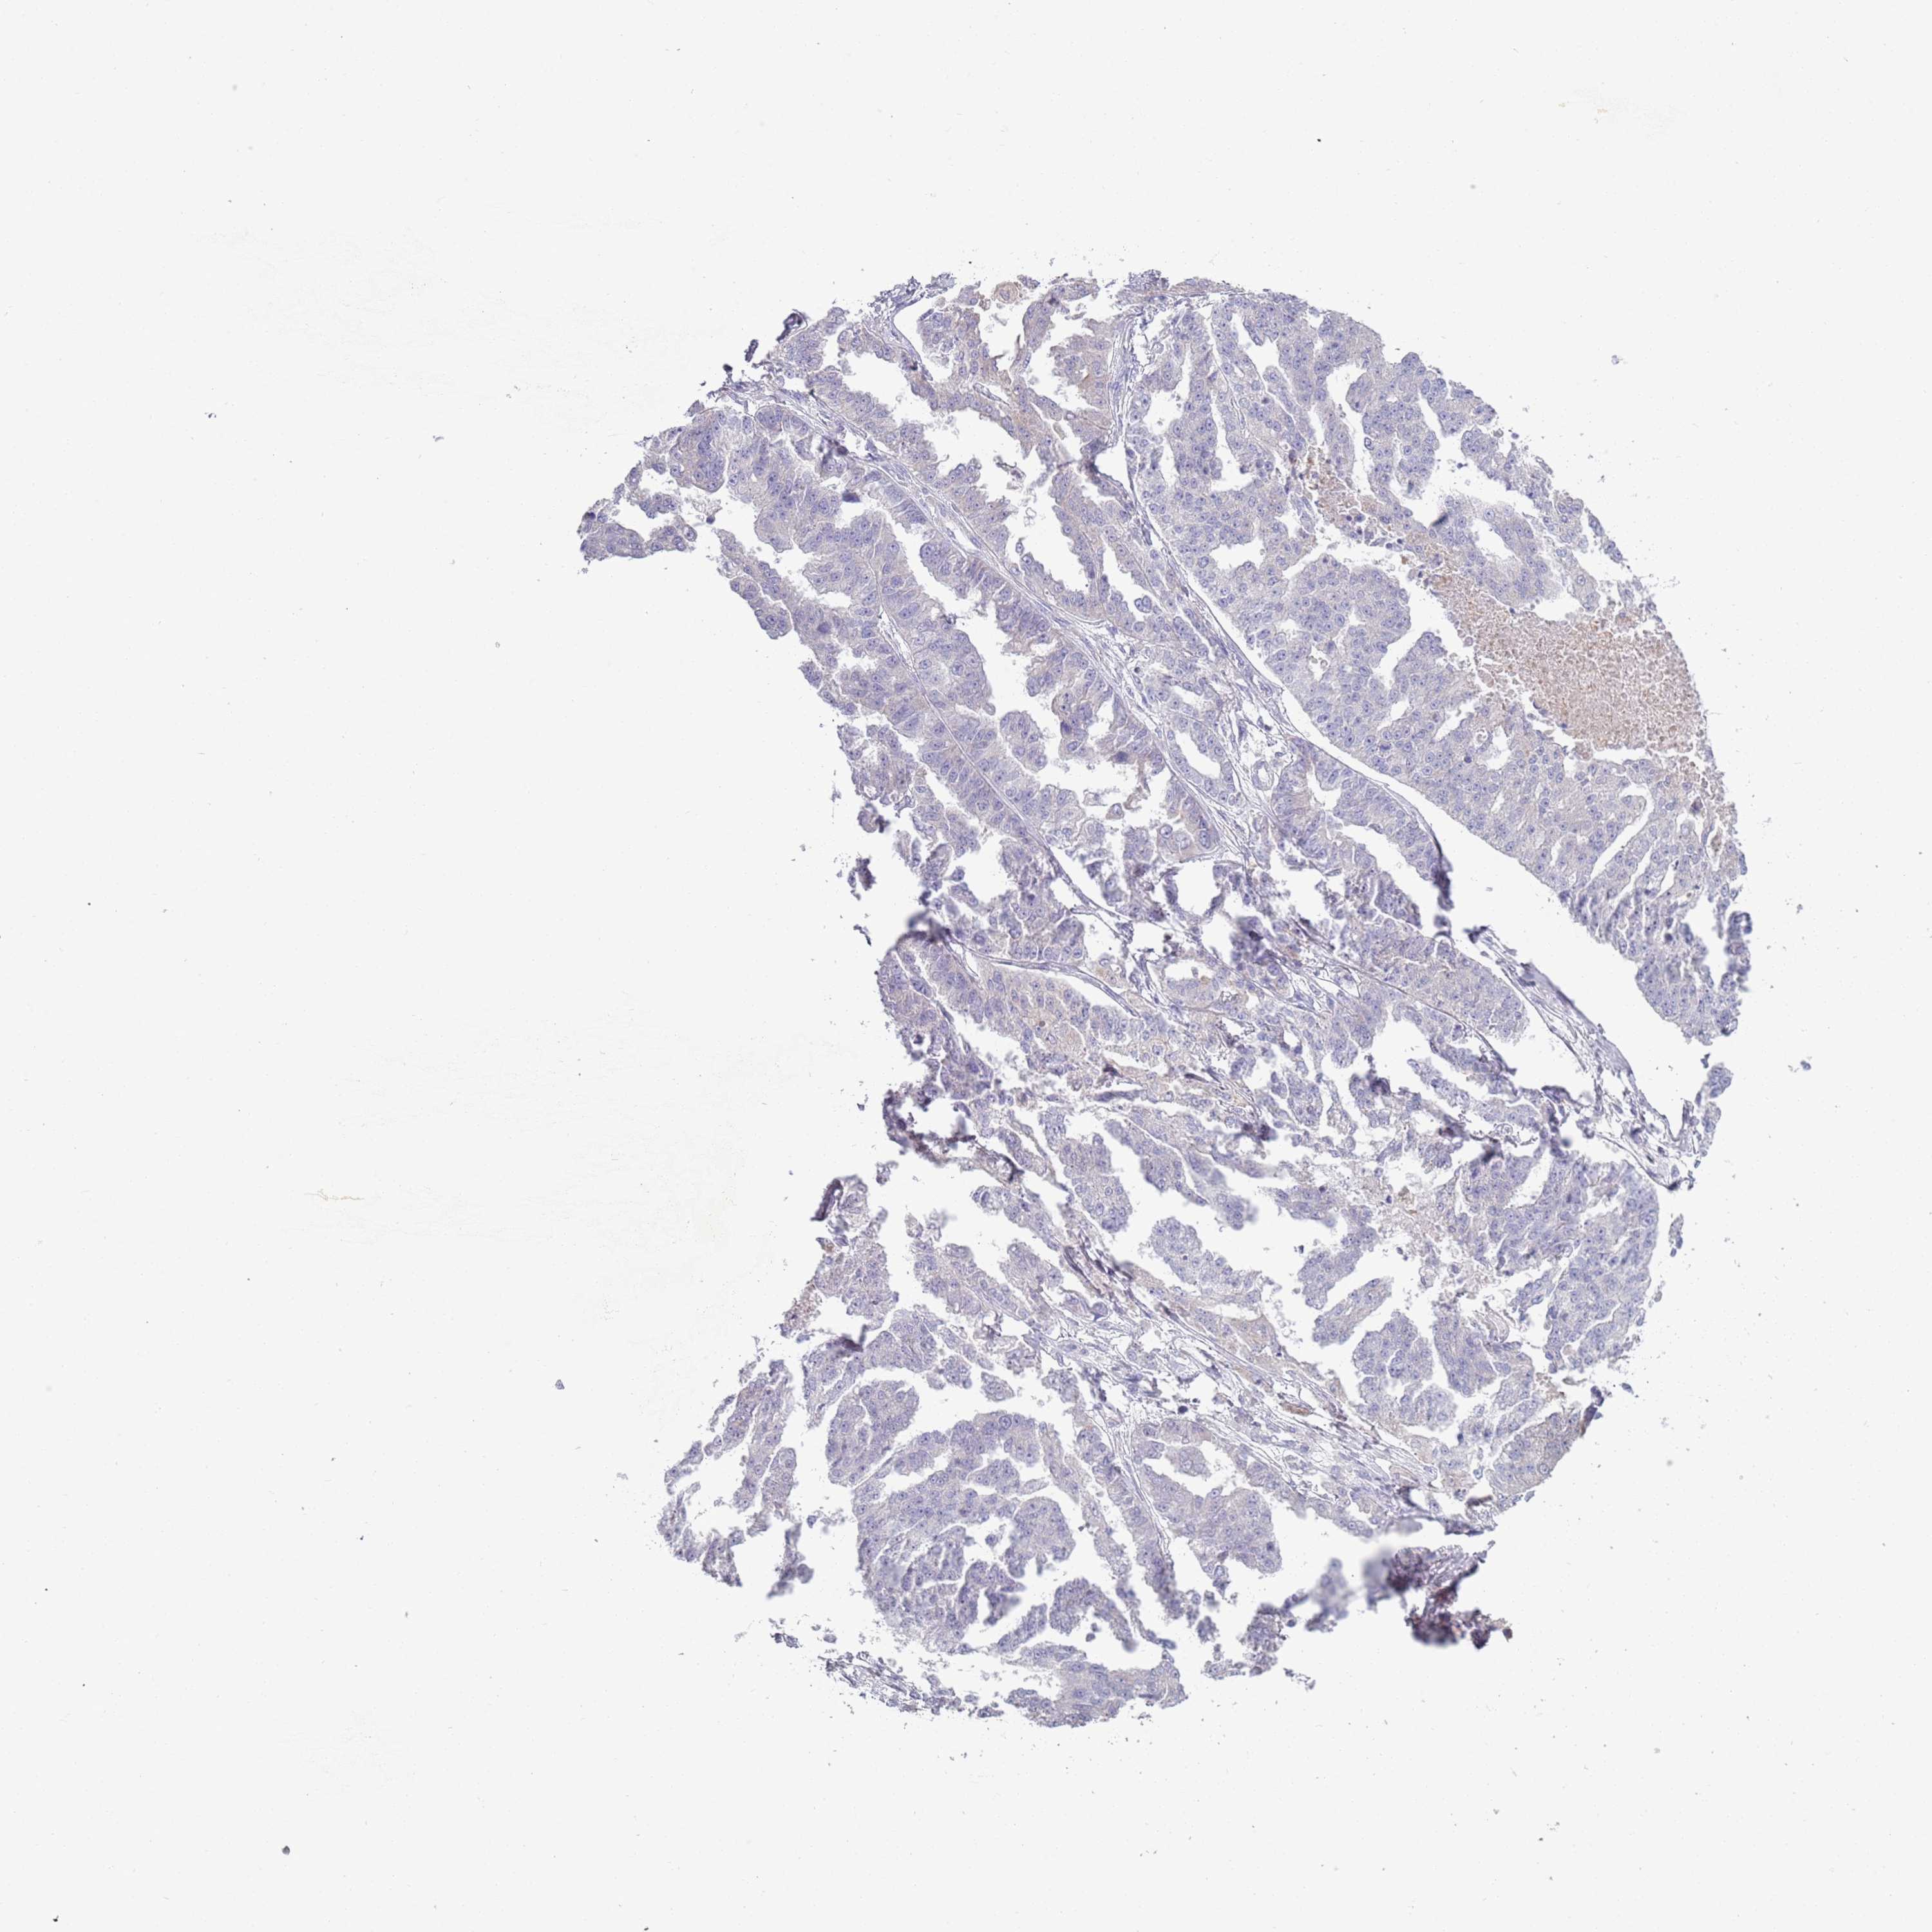

OVARIAN CANCER - Protein expressioni

A mouse-over function shows sample information and annotation data. Click on an image to view it in a full screen mode. Samples can be filtered based on level of antibody staining by selecting one or several of the following categories: high, medium, low and not detected. The assay and annotation is described here.

Note that samples used for immunohistochemistry by the Human Protein Atlas do not correspond to samples in the TCGA dataset.

Antibody stainingi

Antibody staining in the annotated cell types in the current human tissue is reported as not detected, low, medium, or high, based on conventional immunohistochemistry profiling in selected tissues. This score is based on the combination of the staining intensity and fraction of stained cells.

Each image is clickable and will lead to virtual microscopy that enables deeper exploration of all samples and also displays staining intensity scores, fraction scores and subcellular localization as well as patient and tissue information for each sample.

Antibody HPA048884

Staining

High

Medium

Low

Not detected

Intensity

Strong

Moderate

Weak

Negative

Quantity

>75%

75%-25%

<25%

None

Location

Nuclear

Cytoplasmic/membranous

Cytoplasmic/membranous,nuclear

Cystadenocarcinoma, serous, NOS

Carcinoma, NOS

Cystadenocarcinoma, mucinous, NOS

Carcinoma, endometroid